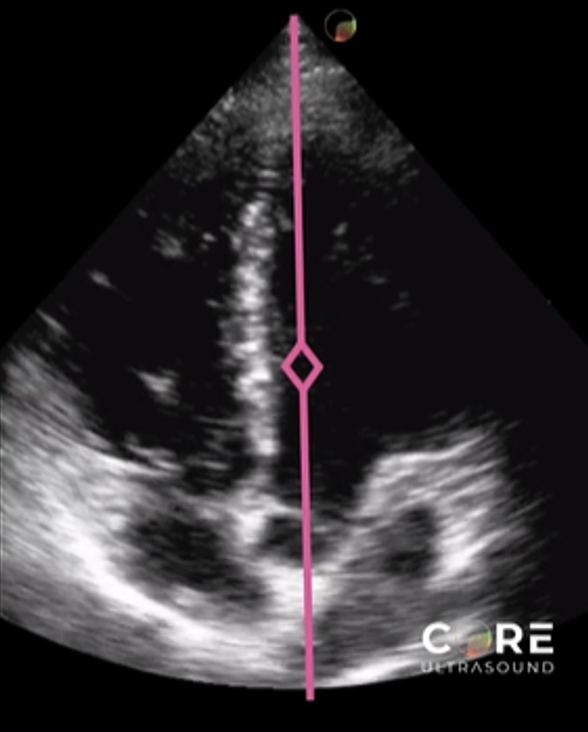

Finding #2: Asymmetrical septal hypertrophy

• View: PSL or PSS View

• Look for a ratio between the interventricular septum/posterior wall thickness

• Ratio > 1.3 in normotensive patients is consistent with HCM

• Ratio > 1.5 in hypertensive patients is consistent with HCM

Left image shows how to measure the septal wall and LV wall in the PSS view. Right image shows the same in the PSL view.